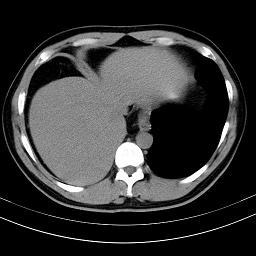

标题: CT18388:肝脏膈肌间隙内大量脂肪密度影 [打印本页]

标题: CT18388:肝脏膈肌间隙内大量脂肪密度影

是脂肪不是气体,有时候会碰到这样的病人,脂肪过多吧。

膈下脂肪沉积。

考虑膈下脂肪沉积。

激素治疗的病人容易脂肪沉积